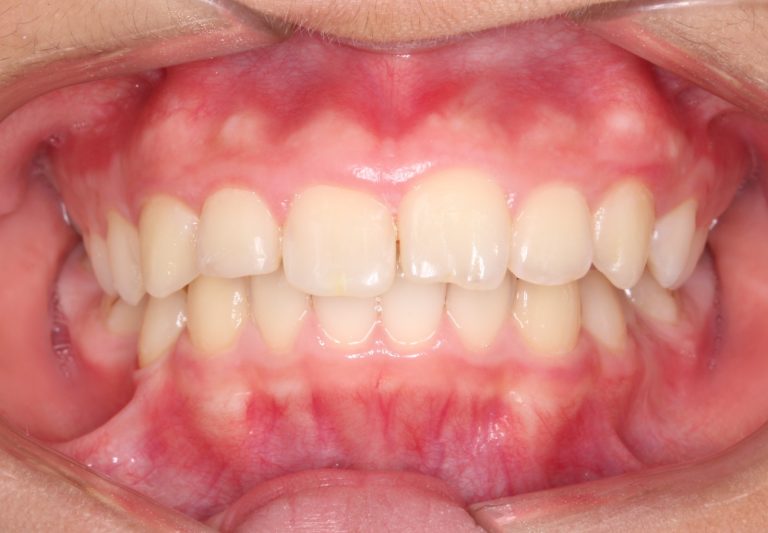

Classe II div 1, surplomb accru, rétrognathie mandibulaire, articulation profonde, arcades étroites, arcades asymétriques, déviation de la ligne médiane mandibulaire, décalage de la ligne médiane, chevauchement

État initial

État final